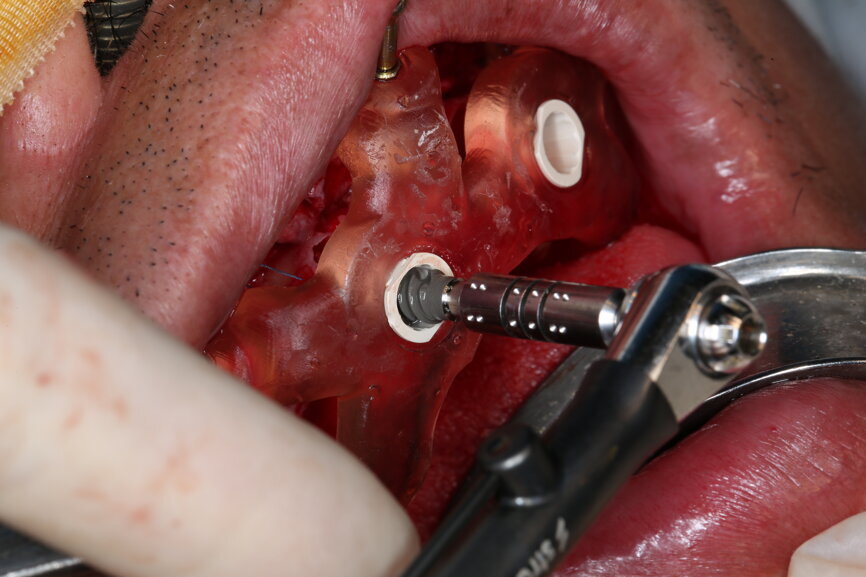

On the day of surgery, we prepared for the surgical protocol provided by the implant planning software, which guided us on the drilling sequence and the use of the appropriate instruments for the implant bed preparation (Figs. 30a & b). After the fixation pins had been allocated, teeth #17, 16, 15, 13, 12, 22, 23 and 24 were atraumatically extracted and alveolectomy was performed using a bone reduction guide (Figs. 31–36). Four implants (Straumann BLX; regular base; diameter: 4.5 mm; length: 12.0 mm) were placed, two straight implants in the anterior and two titled implants in the posterior. All the implants were stabilised to a torque of 50 Ncm (Figs. 37–43), and the SRAs were placed on top. The SRAs on the posterior implants had an angulation of 30° (diameter: 4.6 mm; gingival height: 3.5 mm) and on the anterior implants an angulation of 17° (diameter: 4.6 mm; gingival height: 3.5 mm; Figs. 44 & 45).

The bite registration guide was fixed with pins, and the open-tray impression copings were placed on the SRAs of the anterior implants, which were fixed with the guide using flowable composite and then sent to the laboratory (Figs. 46–50). Afterwards, we checked the CAD/CAM temporary restoration which had been designed and milled before surgery (Fig. 51), and protective caps were placed on the SRAs, followed by bone grafting using cerabone granules (botiss biomaterials) with a 1–2 mm grain size in the extraction sockets and suturing (Figs. 52–54).